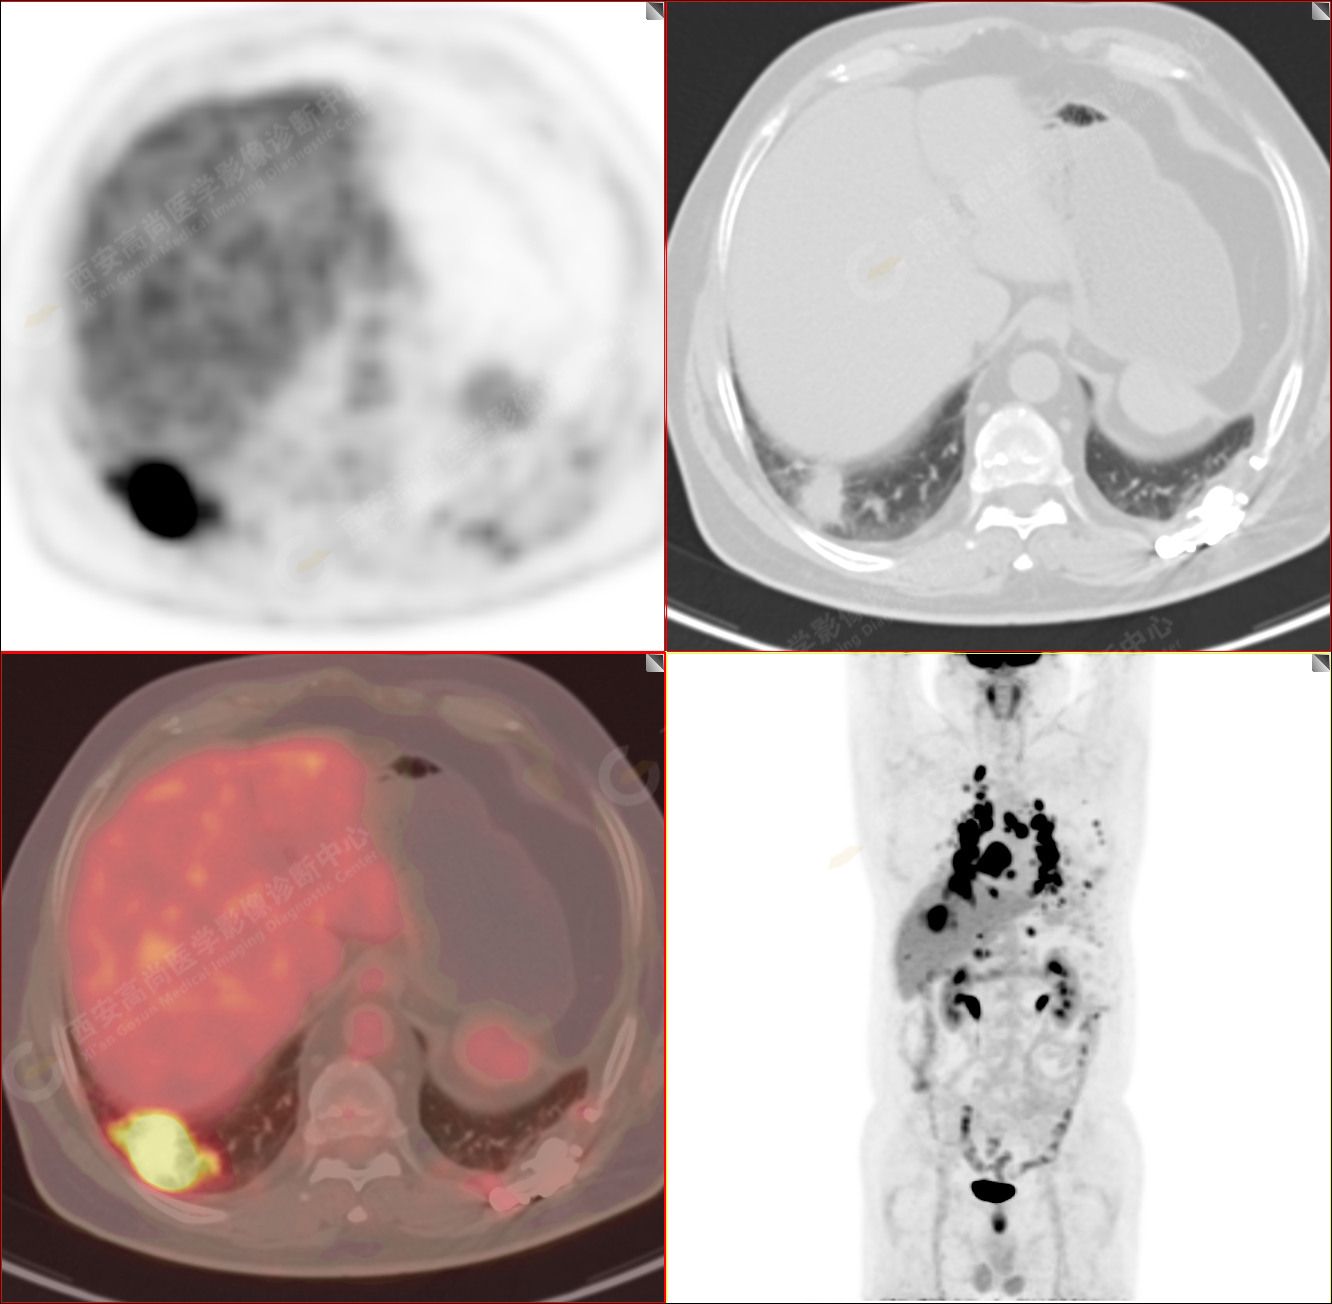

男性,53歲,頭暈半月入院,CT發(fā)現(xiàn)肺內(nèi)腫塊,雙肺多發(fā)大小不等實性及粟粒樣結(jié)節(jié),雙肺門及縱隔多發(fā)腫大淋巴結(jié)。病程中無發(fā)熱、胸悶氣及胸部不適。既往:左側(cè)肋骨外傷史。

PET-MR圖像